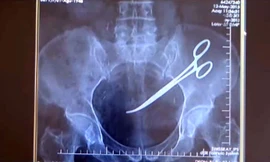

TPO - Bà Hanim Ozgul, 67 tuổi người Thổ Nhĩ Kỳ tá hoả khi phát hiện có một chiếc kéo phẫu thuật nằm trong ổ bụng của mình từ sau ca phẫu thuật điều trị ung thư cách đây 5 năm.